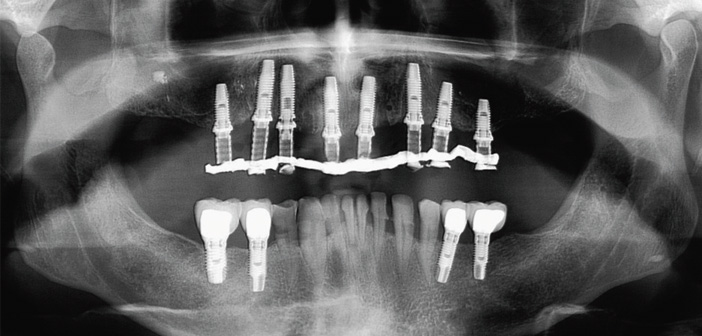

Après étude de votre cas grâce à notre imagerie scanner dernière génération nous pouvons réaliser une planification implantaire.

Si l’ensemble des dents doit être remplacé par des implants, nous pouvons réaliser des traitements de l’arcade complète appelés « all on 4 » ou « all on 6 » ; ceci permet de remplacer l’ensemble des dents d’une arcade avec 4 ou 6 implants si la situation le permet.

La chirurgie guidée permet de poser les implants à l’aide d’un guide, ce qui rend la chirurgie plus sure et précise, elle permet de proposer la mise en place de provisoires immédiatement le jour de la chirurgie sir la stabilité de l’implant le permet.